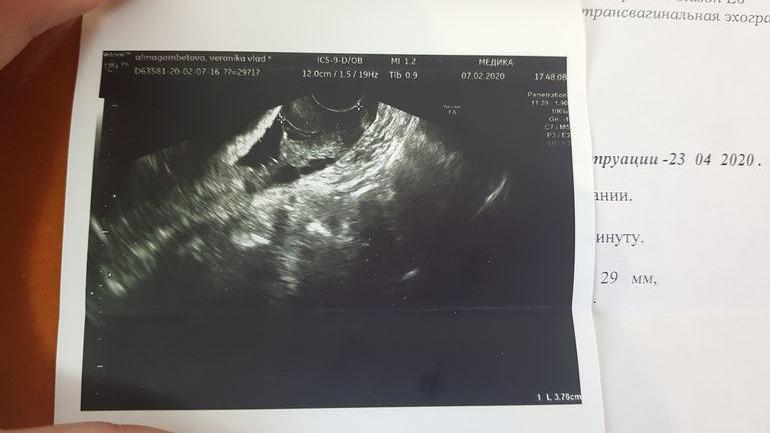

Девочки, всем привет. Может кто-нибудь разбирается в цервикометрии ? Мой врач меряет мне шейку каждые 4 дня и у нее то 27, то 33, последний раз было 30. Я уже устала и поехала померить платно, пришла к ней с результатами, она посмотрела фото и сказала что все померено неверно, хочет во вторник меня отправить в роддом на госпитализацию. Но из роддома меня 2недели назад выписали и сказали, что с шейкой все в порядке...я в панике уже, не знаю что и делать..

Езжайте в 1 рд, тут именно по шейкам спецы. Лишних манипуляций делать не будут для подстраховки, но если есть реальная угроза сделают все как надо. По фото мне тоже кажется измерено не правильно. У вас там общая длина шейки, а надо ориентироваться на сомкнутую часть. Если не хотите ложиться, то можете просто придти на консультацию к ним, правда она будет платная. Я второй раз здесь лежу (с разницей в две недели), последний раз из-за перестраховки гинеколога, но в рд сказали что все в пределах нормы для моего срока, но тк уже поступила в стационар решила полежать, а так если время экономите можно просто на консультацию, а там по ситуации решать.